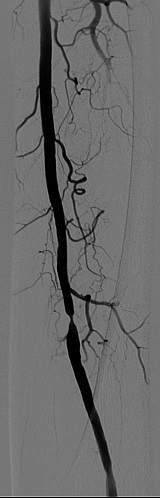

One option of performing revascularization is the percutaneous transluminal angioplasty (PTA):

- Incision is made below the inguinal line (where the leg folds near pelvis), and a guidewire with balloon is inserted into the vessel. There is the noncomplicant balloon, (which can handle a large pressure and expands to certain volume), and a compliant balloon (which can expand up to 800% of its nonstretched volume). For angioplasty we use the noncompliant balloon.

- The guidewire goes through the site of occlusion, until the segment with the deflated balloon lies in its lumen.

- The balloon is then expanded, widening the occlusion/stenosis.

- Stents are then placed, to maintain the dilation of vessel; either having expanded with the balloon, placed to expand by itself and fit the 'mold', or drug-eluting (paclitaxel or sirolimus-releasing, to chemically prevent the vessels from closing again (block cell division at vessel wall).

During the angioplasty procedure, it is important to view in real time where the guidewire is going and where the balloon is placed. X-ray fluoroscopy allows this by obtaining real-time images; wires can be seen moving through this type of imaging.